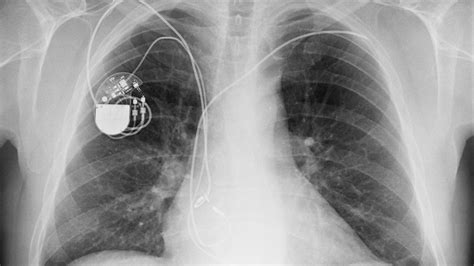

Frank Stephenson Blog